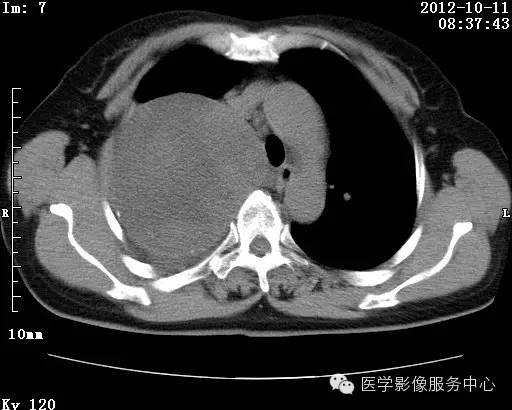

【病例】右肺巨大错构瘤1例CT影像表现

病史:女 65岁咳嗽咳痰 右肺巨大肿块就诊。

错构瘤的发病年龄多数在40岁以上,男性多于女性。 绝大多数错构瘤(约80%以上)生长在肺的周边部,紧贴于肺的脏层胸膜之下,有时突出于肺表面。其特征钙化为爆米花样钙化,内有脂肪软骨成分等等。最常见的部位是胸膜下肺实质内,其次为主支气管或肺叶、肺段支气管内。

由于不典型错构瘤极易误诊为周围型肺癌和/或结核球,故应与二者鉴别。

结核球患者既往病史中可能有明确的肺结核病史,周围多可见卫 星病灶,增强扫描无强化或仅有包膜强化,此外纵隔 肺门淋巴结多有钙化征象;

周围型肺癌绝大多数边界不光整, 可见短毛刺,钙化不常见,爆米花样钙化更罕见,而 且往往合并有纵隔肺门淋巴结增大增多,患者临床症状较为明显。